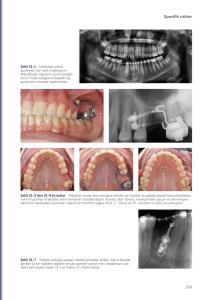

21 x 28 cm; 26 video, 312 sayfa, 450 resim